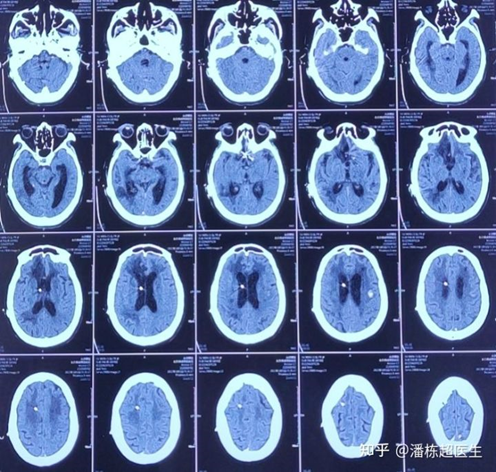

今天讲的这个病例,是一位79岁的脑积水患者,在北京全国顶级医院做了脑室腹腔分流术。术后脑室有缩小但患者状态却一直不好,反复调压两个月,调完后可能有几个小时状态好转,随后再次嗜睡、浅昏迷。

按压分流泵很通畅,术后反复调压两个月不见改善,腹部ct没有问题,体温正常。患者长期呼吸费力,躁动,嗜睡,后又继发颅内出血。如果状态不能改善,医生和家属都将看不到一点希望。